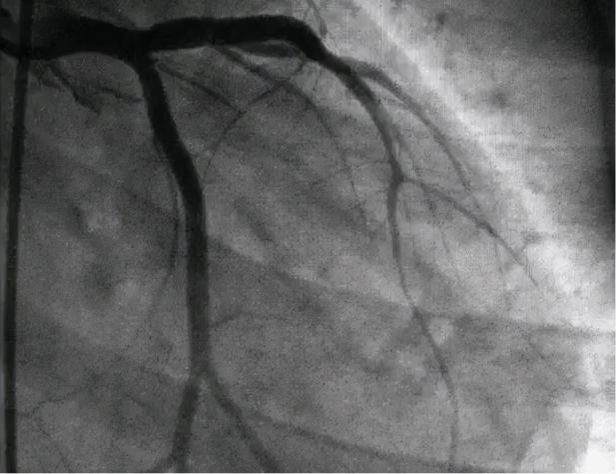

1. 冠状动脉介入诊疗技术

(1)冠状动脉造影检查能快速了解血管狭窄病灶,指导治疗方案及疗效判断。

(2)冠状动脉腔内支架植入术(PCI)是在冠状动脉造影检查基础上利用支架球囊导管撑开血管壁恢复血流。

冠状动脉造影术

择期冠状动脉腔内支架植入术